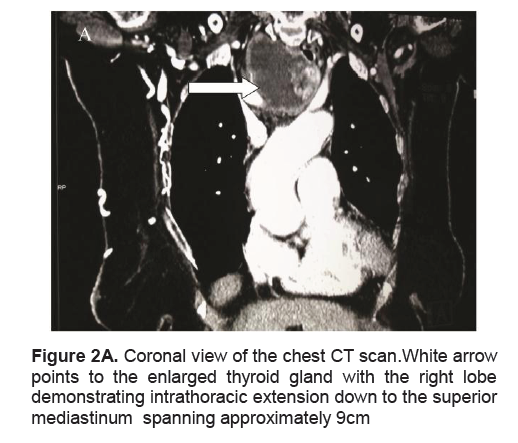

A frail, 71-year-old female in mild respiratory distress presented at the Emergency Room. Her condition started 2 weeks prior to consult she started to experience shortness of breath and easy fatigability. Pertinent in the history was a goiter which was untreated for several years. There was no noticeable rapid enlargement of the thyroid gland, but there was hoarseness for the past 15 years. She noted weight loss in the last 8 months. She had no prior history of neck radiation, nor family history of goiter. Palpitations and easy fatigability were also present. At the time dyspnea became progressive, patient became weak, and appetite started to decrease. Physical examination showed she was tachycardic, tachypneic, febrile with wheezing and crackles on both lung fields. No palpable thyroid nodules and no cervical lympadenopathy were appreciated. Initial impression was pneumonia with marked leukocytosis at 22.70mg/dl with toxic granules. Chest x-ray showed pulmonary nodules and right superior mediastinal mass, inflammatory versus neoplastic in origin. Thyroid function test results showed suppressed TSH 0.01uIU/mL (normal 0.35-4.94uIU/mL), FT3 6.37pg/mL (normal 1.45-3.48), and elevated FT4 2.36 ng/dL (normal 0.71-1.85). Patient underwent thyroid scan which showed non-hyperactive multinodular goiter with cold nodules dominant on the right and focal hot areas in both lobes suggestive of goitrous thyroiditis (Figures 1A, 1B, 1C). Thyrotropin receptor antibodies were negative. Ultrasound of the thyroid revealed bilateral thyroid nodules. The right lobe showed three solid nodules with the following measurements: 2.1 x 1.8 x 1.10 cm (with peripheral vascularity), 3.7 x 3.3 x 2.0 cm, and 5.0 x 3.7cm (with calcifications and minimal internal and peripheral vascularity). Left lower thyroid lobe had complex nodules with the following measurements: 2.0 x 2.4 x 1.8 cm (predominantly solid) and 4.2 x 3.3 x 2.4 cm (with peripheral vascularity). Treatment for her thyrotoxicosis was started with propylthiouracil 50mg/tab 4 tabs every 8 hours. With persistent shortness of breath, a chest CT scan with intravenous contrast was done and it showed several mildly enhancing, well circumscribed pulmonary nodules in both lung fields. The largest nodule measured 1.5cm in its widest diameter, while most of the nodules were subcentimeter in diameter. The enlarged right thyroid lobe spanned an approximate length of 9cm and extended into the superior mediastinum. (Figure 2A). The mass compresses the mid segment of the trachea to the left, narrowing its lumen (Figure 2B). After several days of treatment with antibiotics and anti-thyroid medications, the patient had improved and dyspnea had markedly lessened.

Figure 2A. Coronal view of the chest CT scan.White arrow points to the enlarged thyroid gland with the right lobe demonstrating intrathoracic extension down to the superior mediastinum spanning approximately 9cm